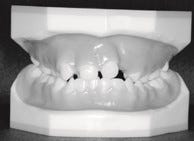

De fase dat de orthodontist in beeld komt is wanneer de eerste tanden gaan wisselen, op de leeftijd van ongeveer zes jaar. Bij uw bezoek aan het schisisteam wordt dan een röntgenfoto gemaakt om te zien welke tanden en kiezen zijn aangelegd. Ook als het melkgebit redelijk normaal is doorgekomen, zie je bij gehemeltespleten de tanden vaak scheef doorkomen. Soms is er sprake van een zogenoemde ‘dwangbeet’ (zie foto hieronder). De onderkaak sluit dan niet gemakkelijk tegen de bovenkaak, maar maakt een afglijdende beweging. De reden is dat de bovenkaak meestal te smal is ten opzichte van de onderkaak. Als de kaak wat te smal is verbetert de orthodontist de kaakstand met een beugel.